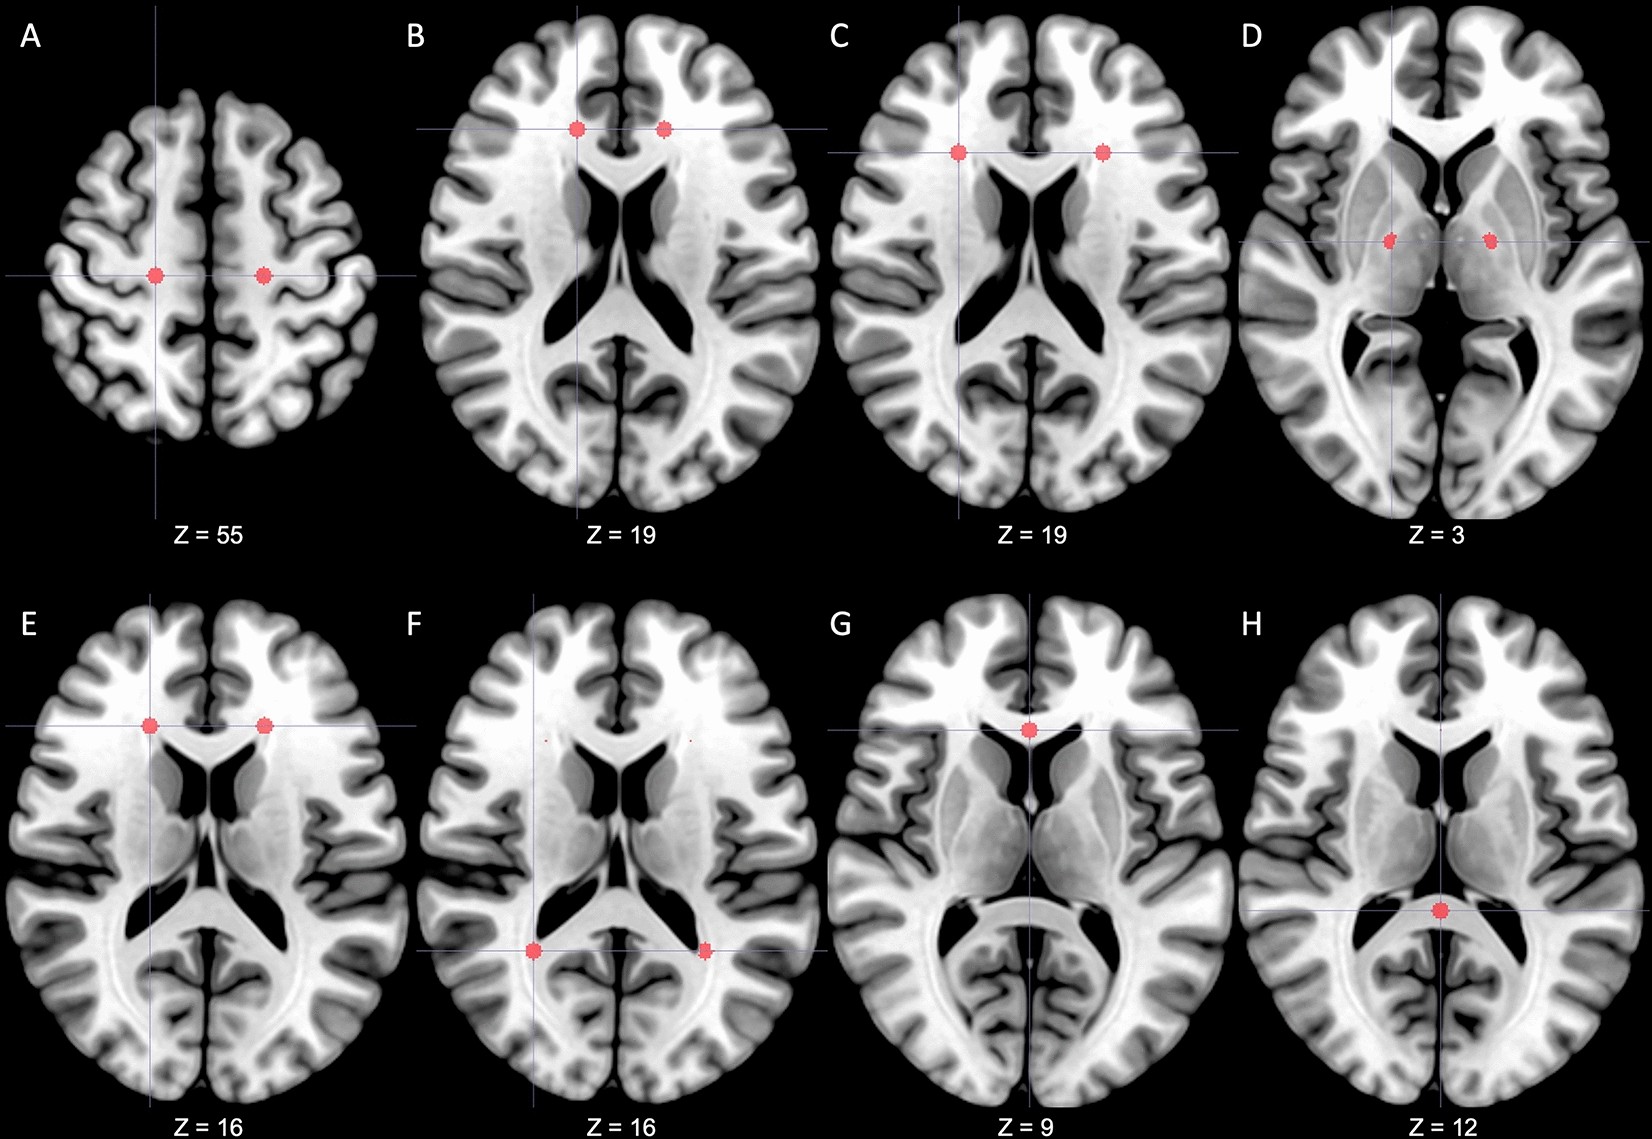

Figure 2

Predetermined regions-of-interest. A total of 14 regions of interest were predetermined in the centrum semiovale (A), anterior area of corona radiata (B), lateral area of corona radiata (C), posterior limbs of the internal capsule (D), anterior horns of the lateral ventricle (E), posterior horns of the lateral ventricle (F), genu of corpus callosum (G) and splenium of corpus callosum (H). From a radiological perspective, the right side of the figure is the patient's left side. The z coordinate represents the position on the MNI152 standard template. MNI Montreal Neurological Institute.